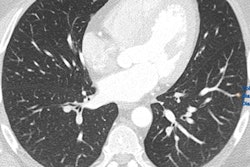

"As radiologists, when we look at CT images we see light and dark areas and we assess the organ using these differences in brightness," said Dr. Joshua Gawlitza, a researcher from the Institute of Clinical Radiology and Nuclear Medicine at Mannheim, who reported the group's findings.

Left: Regular CT for suspected COPD. Right: Overlaid qCT. The blue areas represent the typical "air trapping" seen in COPD. The red sections only show vessels and have no pathological value. All images courtesy of Dr. Joshua Gawlitza.Software programs, which have long been helping radiologists evaluate CT images, usually assess density differences on CT scans and determine average values for the relevant regions.

"In this process, the software does not just evaluate average densities, but instead analyzes each individual pixel or 'voxel' separately and links them together," Gawlitza explained.

This can prove very interesting in an organ like the lungs, where the qCT evaluates more than two million voxels per lobe, he added. In patients with chronic obstructive pulmonary disease (COPD), for example, the lung is not evenly ventilated. Instead there are areas where the air becomes "trapped" as the patient breathes out, and other areas that work almost normally.

"These badly ventilated areas can be identified with the qCT," Gawlitza noted.